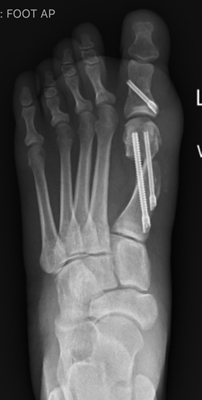

TOTAL ANKLE REPLACEMENT :: ORIF CALCANEUS :: ORIF ANKLE FRACTURE DISLOCATION :: COMPLEX BUNION AND LESSER TOE CORRECTION :: TALUS FRACTURE -1 :: TALUS FRACTURE -2 :: LISFRANC REPAIR :: COMPLEX TRIPLE ARTHRODESIS 1 :: COMPLEX TRIPLE ARTHRODESIS 2 :: MINIMALLY INVASIVE BUNION REPAIR 1 :: MINIMALLY INVASIVE BUNION REPAIR 2 :: ARTHROSCOPIC CARTILAGE REPAIR :: TENEX SPUR DEBRIDEMENT :: Haglunds Debridement and Achilles Repair